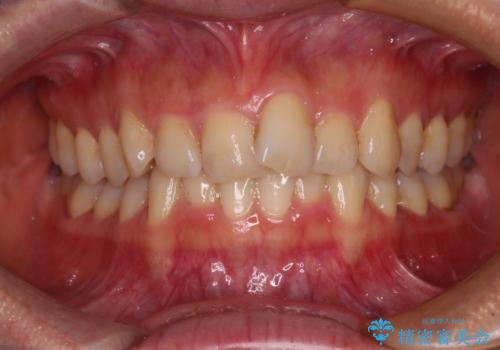

[ マウスピース矯正 ] 出っ歯に見える前歯を改善したい

![[ マウスピース矯正 ] 出っ歯に見える前歯を改善したいの症例 治療前](https://seimitsushinbi.jp/wp/wp-content/uploads/2023/10/IMG_6858-500x350.jpg?v=1697014973)

![[ マウスピース矯正 ] 出っ歯に見える前歯を改善したいの症例 治療後](https://seimitsushinbi.jp/wp/wp-content/uploads/2023/10/8a6c9bf89570c0c75da0a5fabd1cd70e-500x350.jpg?v=1697014858)